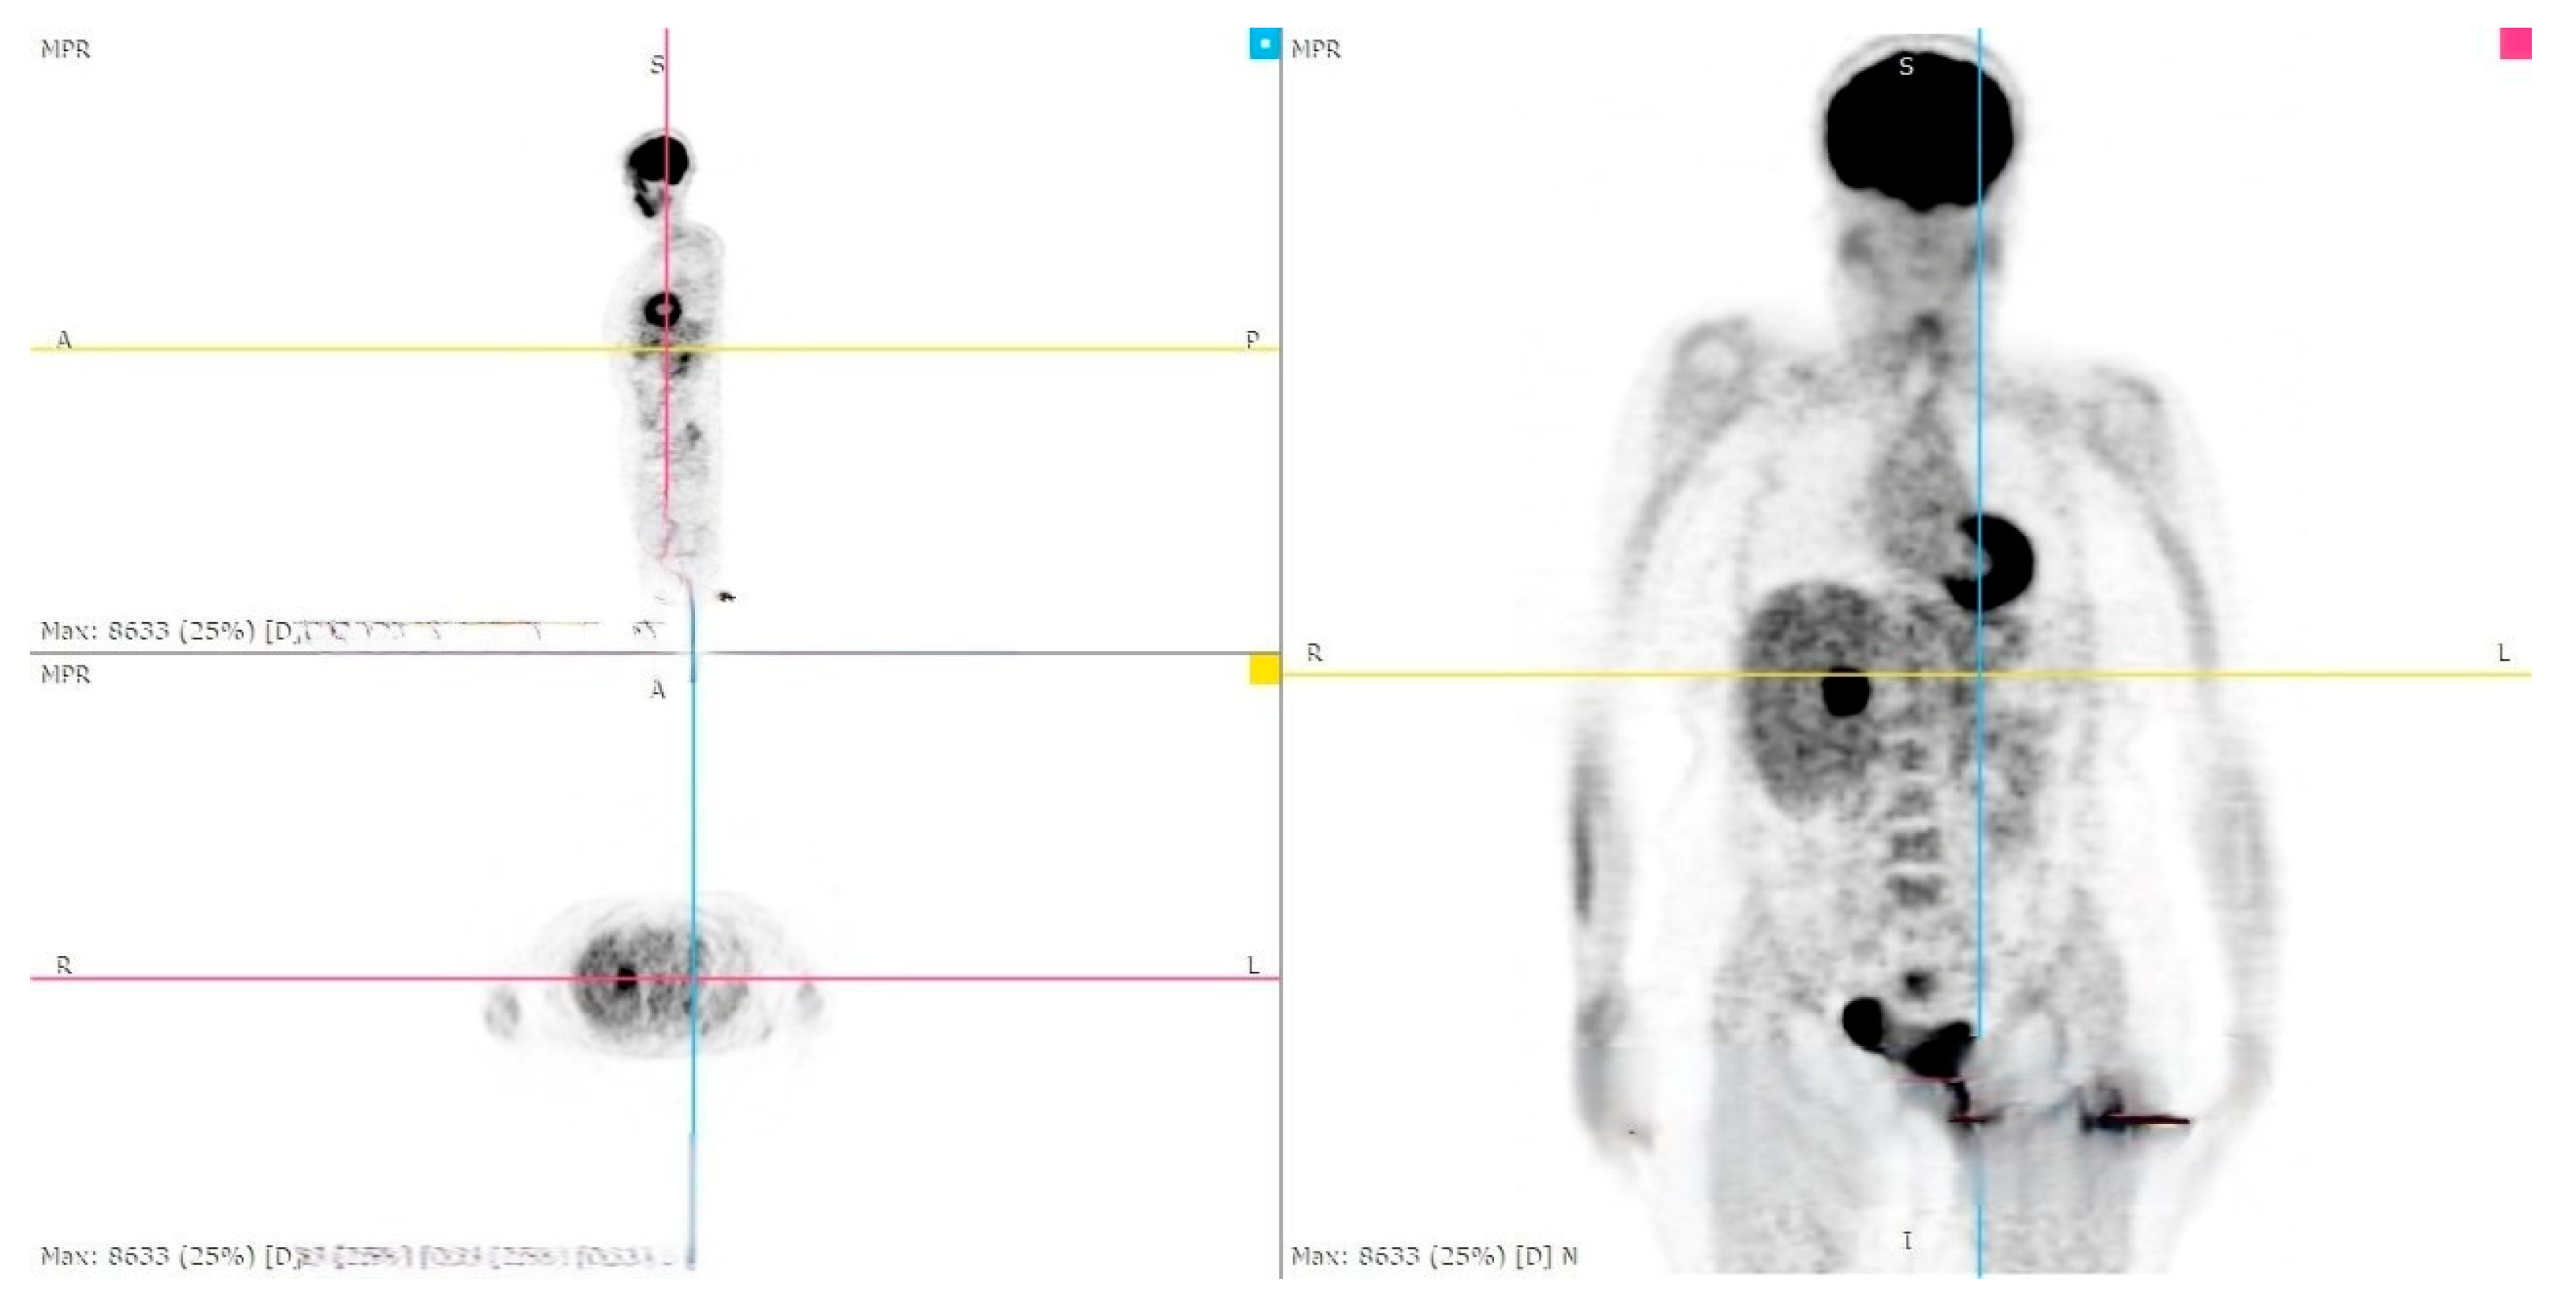

During the follow-up examination at 4 months post-surgery, a PET-CT scan without contrast conducted at another facility revealed a prominent focal hypermetabolic lesion in the hepatic segment V measuring approximately 51 × 44 mm with a SUV of 14.3, indicative of a secondary lesion. Additionally, osteolytic lesions were observed along the lateral aspect of the third rib on the right hemithorax (SUV max 3.5) and the inferior angle of the left scapula (SUV max 3.2), along with multiple bilateral pulmonary nodules (SUV max 1.2) [Figure 5, Figure 6 and Figure 7]. Hence, the aggressive metastatic dissemination of leiomyosarcoma underscores the imperative for a prompt reassessment of the treatment approach and the contemplation of intensified therapeutic interventions.

Figure 6.

PET-CT whole body: hepatic metastasis with a SUV of 14.3.